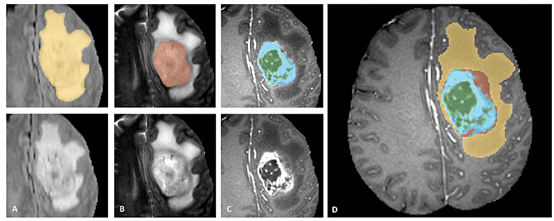

1. BRAST2015数据集介绍

BRAST2015的数据集格式如上图所示,由5个.mha文件构成。其中Flair,T2,T1c,T2为四种模态(理解为四种提取特征的方式),OT为GroundTruth也就是掩码(0,1,2,3,4五种标签)。